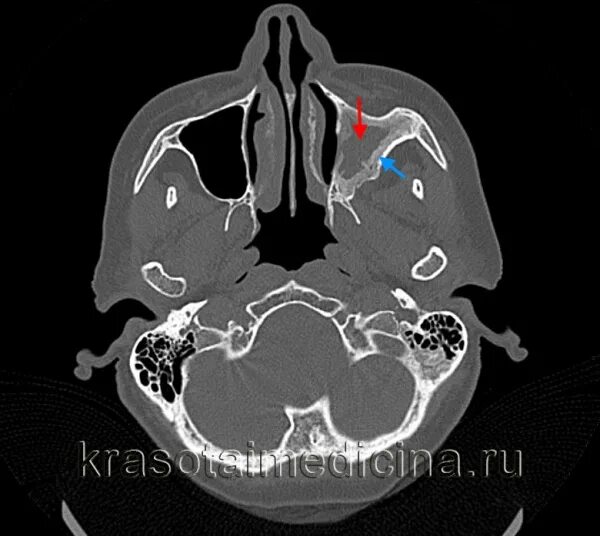

Синусит на кт